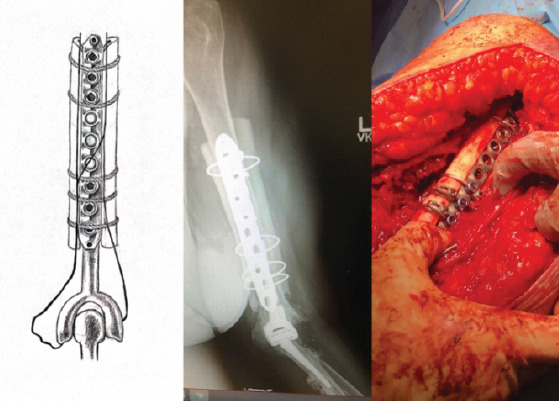

Case report: We present two cases of periprosthetic humerus fractures without implant loosening multiple years after the index procedures. They were treated with open reduction internal fixation (ORIF) utilizing a plate with medial and lateral cortical strut femoral allografting with implant retention.

Conclusion: Two cases of periprosthetic humerus fractures about total elbow arthroplasties were successfully treated with ORIF with medial and lateral cortical strut augmentation. Treatment for periprosthetic elbow fractures should be tailored to each patient based on factors, such as stability of implant, bone stock, and patient goals.